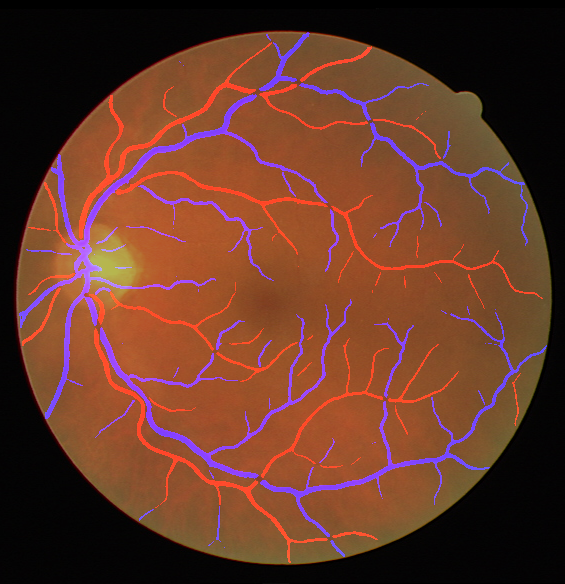

Table V presents quantitative performance benchmarks of SegRAVIR and other competing approaches for retinal artery and vein classification on the RITE dataset [11]. SegRAVIR outperforms previous state-of-the-art approaches in terms of accuracy, sensitivity, and specificity. Fig. 5 provides a qualitative comparison between segmentation outputs of SegRAVIR and the method of Hemelings et al. [40] on the RITE test set.

VI-B Vessel Width Estimation